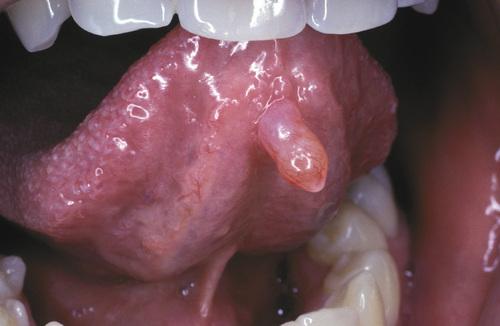

Blue-pigmented nodule on the lower lip. There is often a bluish translucent hue to the swelling, although deeper lesions may be normal in color.

mucocele

Nodule on the posterior buccal mucosa. The reported duration of the lesion can vary from a few days to several years; most patients report several weeks.

mucocele

Exophytic lesion on the anterior ventral tongue from the glands of Blandin-Nuhn. The lower lip is by far the most common site for this type of lesion.

mucocele